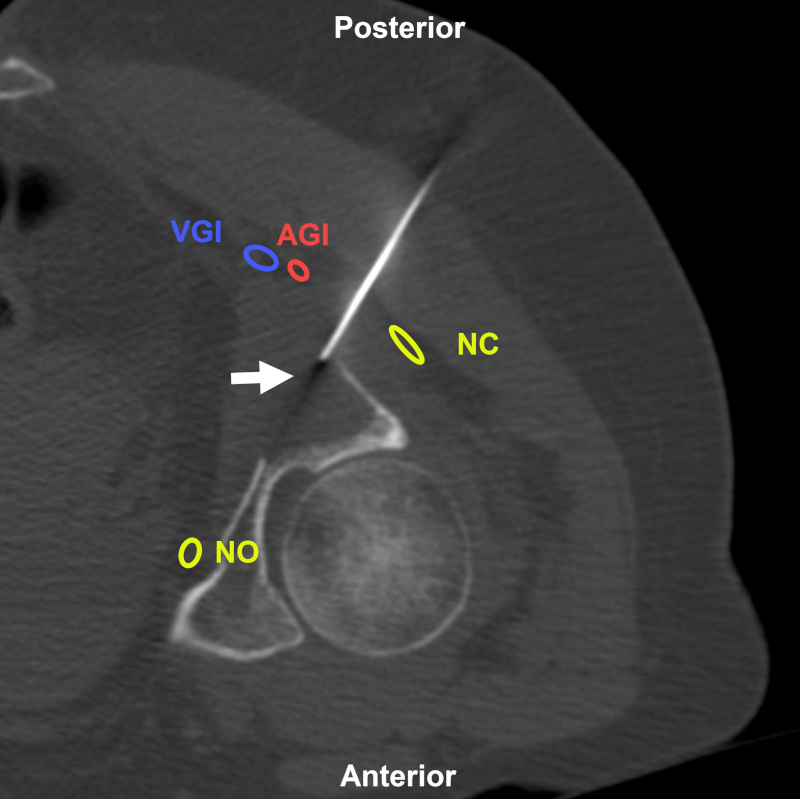

Figura 12

Mujer de 59 años con antecedentes de cáncer de mama en reestadificación por lesión lítica. BP con abordaje directo posterior (flecha) bajo TC. Estructuras a evitar: NC: nervio ciático; AGI: arteria glútea inferior; VGI: vena glútea inferior; NO: nervio obturador. Aguja utilizada: Franseen 18 G. Diagnóstico final: infiltración por adenocarcinoma de origen mamario.